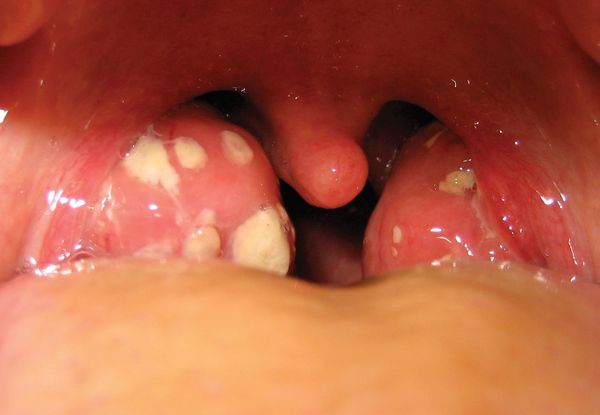

Добавлено: 07.03.2023, 03:23 Источник: ![]() Ангина - это острое общее инфекционное заболевание с преимущественным поражением нёбных миндалин. Воспалительный процесс может развиваться и в других скоплениях лимфаденоидной ткани глотки и гортани — в язычной, гортанной, носоглоточной, миндалинах. Тогда соответственно говорят о язычной, гортанной или носоглоточной ангине. Инфицирование может быть извне или собственными микробами. Возможны два пути передачи инфекции: воздушно-капельный и пищевой. Но чаще всего происходит внутреннее инфицирование из полости рта или глотки ( хроническое воспаление нёбных миндалин, кариозные зубы и др.). Источником инфекции могут быть также гнойные заболевания носа и его придаточных пазух. Наиболее часто возбудителями инфекции являются стафилококк, стрептококк, пневмококк. Есть сведения о возможности вирусных ангин. Предрасполагающие факторы: местное и общее охлаждение, снижение сопротивляемости организма. Ангиной чаще болеют дети дошкольного и школьного возраста и взрослые до 35—40 лет, особенно в осенний и весенний периоды. При простудных заболеваниях и насморке обычно воспаляется также и слизистая оболочка глотки — фарингит. Она становится сухой, красной, раздраженной и набухшей. В таком случае причиной обычно являются вирусы. Однако часто сюда добавляется и вторичная инфекция от бактерий, которые проявляются при ослабленном иммунитете. Наряду с острым воспалением глотки наблюдается, и его хроническая форма. Она вызывается длительным раздражением слизистой оболочки пылью, курением, алкоголем, увеличением миндалин или постоянным дыханием через рот (например, из-за искривления носовой перегородки, при хроническом воспалении придаточных пазух носа). Общие сведения Ангина – группа острых инфекционных заболеваний, которые сопровождаются воспалением одной или нескольких миндалин глоточного кольца. Как правило, поражаются нёбные миндалины. Реже воспаление развивается в носоглоточной, гортанной или язычной миндалинах. По распространенности ангина находится на втором месте после ОРВИ. Чаще развивается весной и осенью. Поражает преимущественно детей и взрослых в возрасте до 35 лет. Причины ангины Возбудители болезни проникают в ткань миндалин извне (экзогенное инфицирование) или изнутри (эндогенное инфицирование). От человека человеку ангина передается воздушно-капельным или алиментарным (пищевым) путем. При эндогенном инфицировании микробы попадают в миндалины из кариозных зубов, придаточных пазух (при синуситах) или носовой полости. При ослаблении иммунитета ангина может вызываться бактериями и вирусами, которые постоянно присутствуют на слизистой рта и глотки. Около 85% всех первичных ангин вызвано ß-гемолитическим стрептококком группы А. В остальных случаях в качестве возбудителя выступает пневмококк, золотистый стафилококк или смешанная флора. Обычно передается воздушно-капельным путем. Вероятность возникновения ангины увеличивается при общем и местном переохлаждении, снижении иммунитета, гиповитаминозах, нарушениях носового дыхания, повышенной сухости воздуха, после перенесенного ОРВИ. Патогенез Общие симптомы ангины обусловлены проникновением в кровь продуктов жизнедеятельности микробов. Микробные токсины могут стать причиной токсического поражения сердечно-сосудистой и нервной системы, спровоцировать развитие гломерулонефрита и ревматизма. Риск возникновения осложнений увеличивается при частых рецидивах стрептококковой ангины. Классификация Первичная ангина (другие названия – банальная, простая или обычная ангина). Острое воспалительное заболевание бактериальной природы. Характерны признаки общей инфекции и симптомы поражения лимфоидной ткани глоточного кольца. Вторичная ангина (симптоматическая ангина). Является одним из проявлений другого заболевания. Поражением миндалин могут сопровождаться некоторые острые инфекционные болезни (инфекционный мононуклеоз, дифтерия, скарлатина), заболевания системы крови (лейкоз, алиментарно-токсическая алейкия, агранулоцитоз). Специфическая ангина. Заболевание вызывается специфическим инфекционным агентом (грибки, спирохета и т. д.). ![]() В зависимости от глубины и характера поражения лимфоидной ткани глоточного кольца выделяют катаральную, лакунарную, фолликулярную и некротическую первичную ангину, в зависимости от степени тяжести – легкую, средней степени тяжести и тяжелую форму ангины. Увеличение и покраснение миндалин. Миндалины отёчные, красного цвета («сочные»), что соответствует катаральному тонзиллиту. Обычно эту стадию заболевания не распознают (не успевают) и яркая визуализация наступает на вторые сутки заболевания, когда в ткани миндалин образуются фолликулы белого цвета, размерами 2-3 мм, возвышающиеся над поверхностью ткани миндалин — развивается фолликулярный тонзиллит. С третьего дня в лакунах появляется отделяемое жёлто-белого цвета (гной) — фолликулярно-лакунарный тонзиллит. Далее при тяжёлых формах возникает некротический тонзиллит: тёмно-серый цвет миндалин, после отторжения гнойно-некротических масс остаются дефекты ткани. ![]() Необходимо помнить, что гнойный налёт при ангине не распространяется за пределы миндалин, легко снимается, не тонет в воде — появление каких-либо других вариантов течения является поводом для сомнения в диагнозе. Как протекает ангина у детей У детей симптомы ангины более выражены, чем у взрослых. Сильнее интоксикация, ребёнок вялый, отказывается от еды, возможны боли в животе, сильные головные боли, тошнота и рвота. Осложнения ангины Осложнения ангины включают пара и метатонзиллярные процессы. В острый период могут возникнуть: - паратонзиллит, паратонзиллярный абсцесс (усиление лихорадки, односторонний характер болей, гиперсаливация, болезненность при открывании рта, асимметрия язычка, односторонний отёк, выраженная гиперемия мягкого нёба); - инфекционно-токсический миокардит (боли в сердце, перебои в его работе, изменение размеров сердца, появление шумов, одышка, повышение ЛДГ на 1-2 нормы); - синусит (воспаление придаточных пазух носа); - медиастенит (воспаление органов средостения — появление боли за грудиной, одышка); заглоточный абсцесс (нагноение лимфатических узлов и клетчатки заглоточного пространства — затруднение глотания, одышка, усиление инотоксикации); - сепсис (полиорганное заражение, циркуляция возбудителя в крови). В период выздоровления: - ревматическая лихорадка (боли в суставах, поражение сердца, почек); - инфекционно-токсический миокардит (чаще при первичной форме — перебои в работе сердца, боли, одышка); - полиартрит (боли в различных группах суставов); - гломерулонефрит (возникает на 8-9 дни болезни — боли в области поясницы, новая волна лихорадки, изменения в анализах мочи); - холецистохолангит (выраженные боли в области правого подреберья, потемнение мочи, пожелтение кожи, тошнота, рвота). Как долго лечится ангина При применении антибактериальной терапии лихорадка и болевой синдром уменьшаются в течение 48-72 часов от момента начала приёма лекарств. Режим и диета. Рекомендации и противопоказания для заболевших Лечение осуществляется в домашних условиях, тяжёлые и осложнённые формы ангины лечатся в стационаре. Режим палатный, диета — общий стол, при выраженном болевом синдроме показана механически и химически щадящая пища, обильное питьё. Народные методы терапии. Лечение ангины народными способами и средствами недоказательной медицины недопустимо — это опасно для жизни и здоровья. Антибиотики — лекарства для лечения ангины Несмотря на длительное и широкое применение антибактериальных препаратов первого поколения бета-гемолитический стрептококк остаётся высокочувствителен к пенициллиновой и аминопенициллиновой группе антибиотиков, которые и являются препаратами первого выбора терапии — к концу вторых суток применения антибиотиков возбудитель уже погибает. При невозможности использования препаратов данных групп возможна замена на цефалоспориновый или макролидный ряд антибиотиков. Еще до визита к врачу нужно приступить к частому, то есть не 3-4 раза в день, а ежечасному, полосканию горла. Для полоскания лучше использовать не лекарственные препараты, а слабый теплый раствор соли. Данное мероприятие будет полезно и на более поздних стадиях болезни, но при ангине врач, как правило, назначает полоскания антибактериальными средствами (например, раствором фурациллина, риваноля, элюдрила). Существовали и раньше, но в настоящее время стали более доступными, многочисленные препараты для сосания (фалиминт, фарингосепт, стрепсилс, таблетки или пастилки с ментолом и др.) и аэрозоли для орошения горла (ингалипт, элюдрил, гексорал и др.). При ангине они значительно уменьшают болезненность и способствуют выздоровлению, но по механизму действия не способны полностью заменить первое лечебное мероприятие, о котором велась речь – полоскание. Во время полоскания гной, микробы и продукты их жизнедеятельности смываются и удаляются, а не проглатываются, как при сосании пастилок. Заболевание обычно сопровождается многочисленными проявлениями бактериальной интоксикации, поэтому показано обильное питье, если нет противопоказаний (высокой гипертонии, сердечной или почечной недостаточности), и постельный режим. Врач при ангине обычно дополнительно назначает антибактериальные препараты для приема внутрь или в виде инъекций. К сожалению, без них обойтись не удается, так как возникновение гнойного процесса в области рото- и носоглотки говорит о том, что часть защитных барьеров человека уже преодолены микробами, и организм нуждается в помощи. В отличие от вирусных инфекций, когда применение антибактериальных препаратов не оправдано, за исключением особых случаев, при ангине они приводят к быстрому подавлению микрофлоры и выздоровлению. Анальгетики (аспирин, анальгин, парацетамол и др.) используют как для борьбы с чрезмерно высокой температурой тела (выше 38,5 С для взрослого), головной болью, так и для смягчения болевых ощущений, которые иногда не позволяют, не только нормально есть, но даже пить жидкость. В таких случаях перед едой заранее принимают анальгетик (таблетку можно растолочь; еще лучше использовать препараты в виде растворимых шипучих таблеток или сиропа – детский панадол, эффералган-УПСА и др.). Если в процессе лечения лихорадка спадает, а боли в горле становятся вполне терпимыми, то указанные препараты лучше отменить. Иногда терапия оказывается настолько эффективной, что на 3-4-й день человек начинает ощущать себя практически здоровым. Однако категорически запрещается в это время бросать лечение и выходить на работу, посещать занятия в учебном заведении. Воспалительный процесс еще далеко не завершен, многие системы организма либо ослаблены, либо находятся в состоянии значительной перестройки (в том числе, иммунитет). Чтобы избежать срыва приспособительных механизмов (фактически, развития осложнений), необходим период восстановления, который продлится еще несколько дней. В это время будут весьма кстати хорошее питание, послеобеденный отдых, полноценный сон. В противоположной ситуации, то есть когда состояние больного на фоне лечения не улучшается, или наблюдается усиление болей, лихорадка отличается стабильностью, появляется гнусавость голоса, препятствие при проглатывании пищи или при дыхании или любые другие неприятности, становится крайне необходимым срочная дополнительная консультация врача. Смотрите видео Все про гнойную ангину: симптомы и лечение |